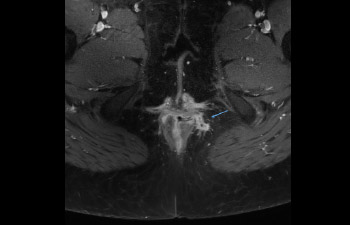

Pelvis image

Pelvis with fistula